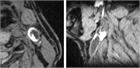

1. プラークの性状評価の診断法についてMRI画像所見を追加し、加筆した。

1. 典型症例として症候性内頚動脈狭窄について画像を用いて解説した。詳細は本文を参照されたい。